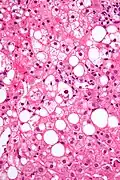

Liver micrograph showing abundant Mallory bodies, as seen in alcohol use disorder. -